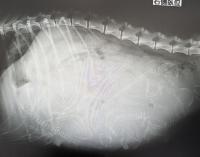

レイちゃん頭数確認にレントゲン検査行ってきました、6頭の天使達がいましたこちらは今週末あたりの出産予定ですみんな無事に生まれてきますように!